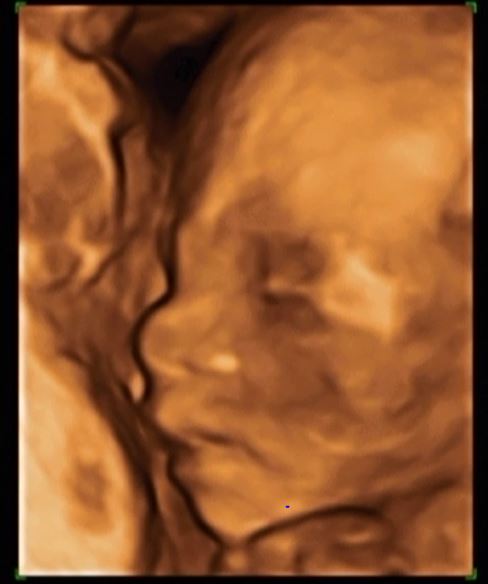

Przedstawiam Jana :D na ostatnim zdjęciu wiecie co... :D